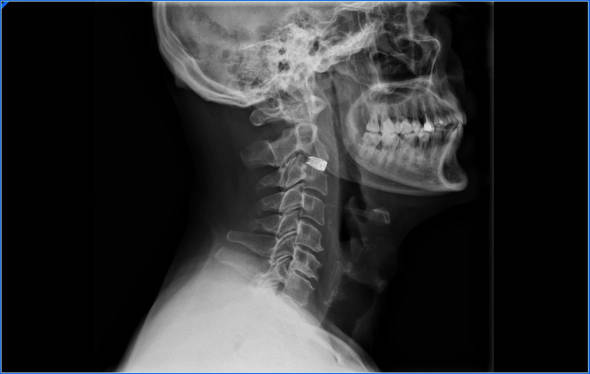

La técnica más utilizada es la artrodesis cervical, está técnica consiste en quitar las estructuras que están comprimiendo la médula. Normalmente el disco y estructuras óseas. Después de descomprimir la médula necesitaremos darle estabilidad al cuello por lo que tendremos que aportar injerto, placas y tornillos.

En determinados pacientes podremos poner una protesis discal, de este modo se mantiene la movilidad, normalmente se utiliza cuando no existe demasiada artrosis cervical.